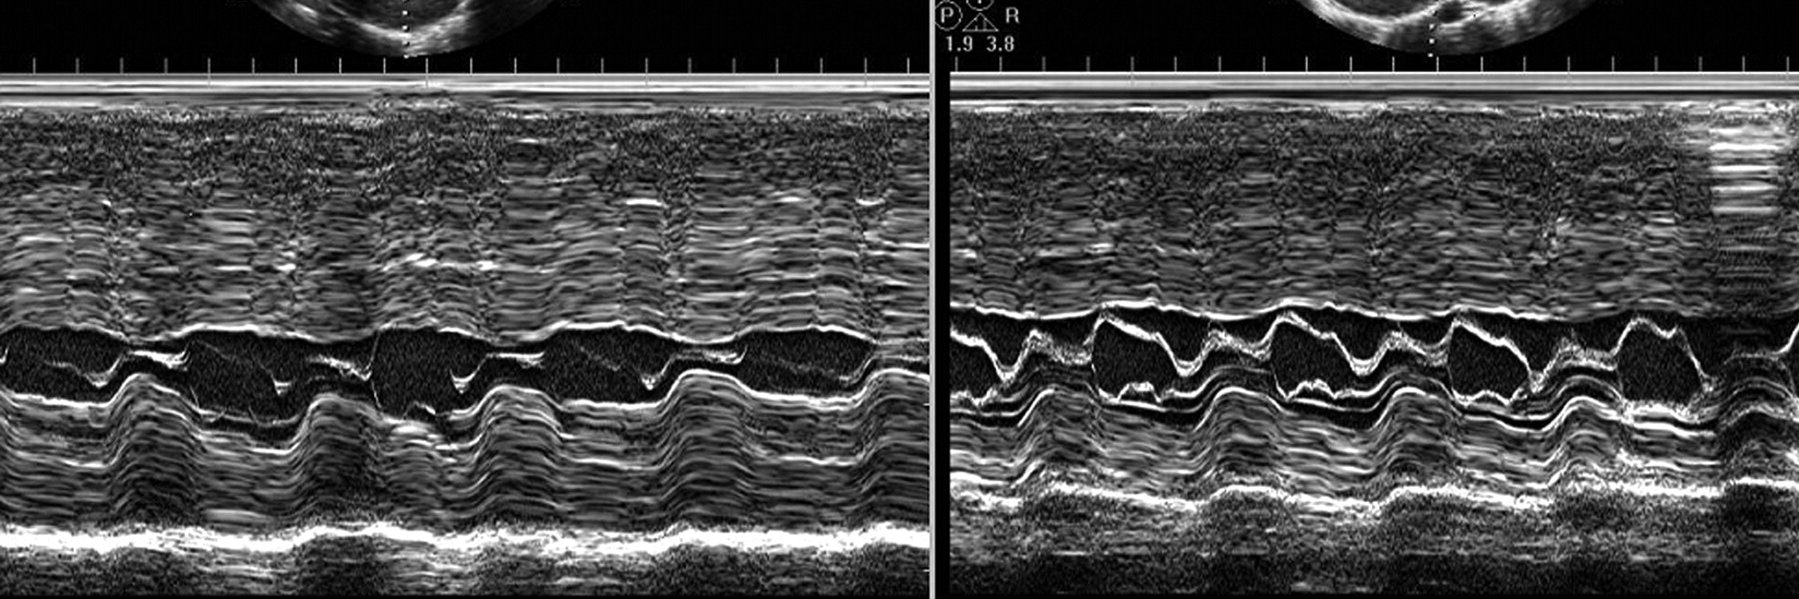

รีทวีตแล้วMariana Brandão@MSBBrandao·2 Oca16-year-old 🤾♂️| What do you see in his #echofirst? @EACVIPresident @Sarah_Moharem @saramoscatelli7 @denisamuraru @NMerke @echo_stepbystep #ACHD #CVImaging #EACVI #CardioTwitterแปล English386323563.2K57